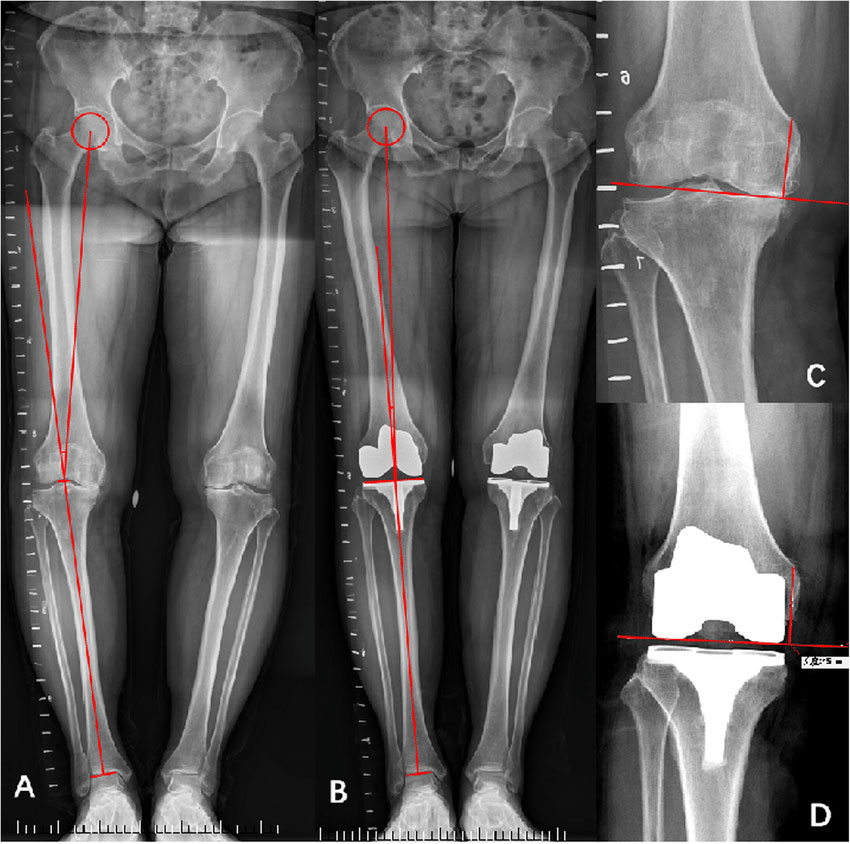

بدشکلی و غیرهمتراز بودن اندامهای تحتانی، بهخصوص پاها، در علم پزشکی با عنوان انحراف از محورهای فيزيولوژيکی تعريف ميشود. این مشکل ممکن است یک علت مادرزادی یا ساختاری داشته باشد. تصویربرداری سی تی اسکن و ام آر آی میتوانند اطلاعات دقیقی در این زمینه ارائه دهند. اما معمولا در مرحله اول پزشکان به سراغ رادیولوژی الایمنت ویو(Alignment view) میروند. چراکه میتواند بخشهای مختلف پاها (لگن، مچ پاها و زانوها) را در قالب یک عکس نشان دهد و به پزشک کمک کند تا انواع مشکل به ویژه انحراف پاها را تشخیص دهد.

اصولاً استخوانهای بدن مانند استخوانهای بلند اندام تحتانی، تحت یک راستا استاندارد و زاویه مشخصی هستند. در علم پزشکی از آن با عنوان الایمنت (alignment) یاد میشود. به عنوان مثال، اگر راستا استخوان بلند پاها تقریبا 2 ± 4 میلیمتر از وسط زانو فاصله داشته باشد، طبیعی است. وقتی اینطور نیست، احتمالا باید به انواع اختلال مانند اختلال پای پرانتزی شک کرد.

رادیولوژیست میتواند این تراز را با کمک رادیولوژی الایمنت، از مرکز لگن تا مرکز مچ پا ترسیم کند و هرگونه بدشکلی را گزارش دهد. البته رادیوگرافی الایمنت برای بررسی طول ستون فقرات و ارزیابی انحراف احتمالی آن نیز گزینه مطلوبی است.